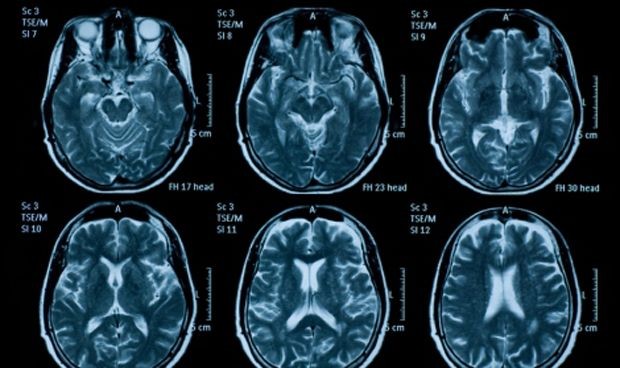

La neuromagen frente a ictus, capítulo clave en el manual

Uno de los temas que se destacan en el manual es la neuroimagen en el ictus en fase aguda, y se defiende el uso de la tomografía computarizada (TC) sin contraste como primer paso del estudio para descartar hemorragia y otras lesiones ocupantes de espacio que puedan simular clínicamente un ictus.

Además, en relación al ictus hemorrágico, los estudios de neuroimagen inicial aportan una información crucial para el diagnóstico de la hemorragia intracraneal, como es la cuantificación del volumen del hematoma, información sobre la etiología y pronóstico sobre la posible expansión del hematoma.